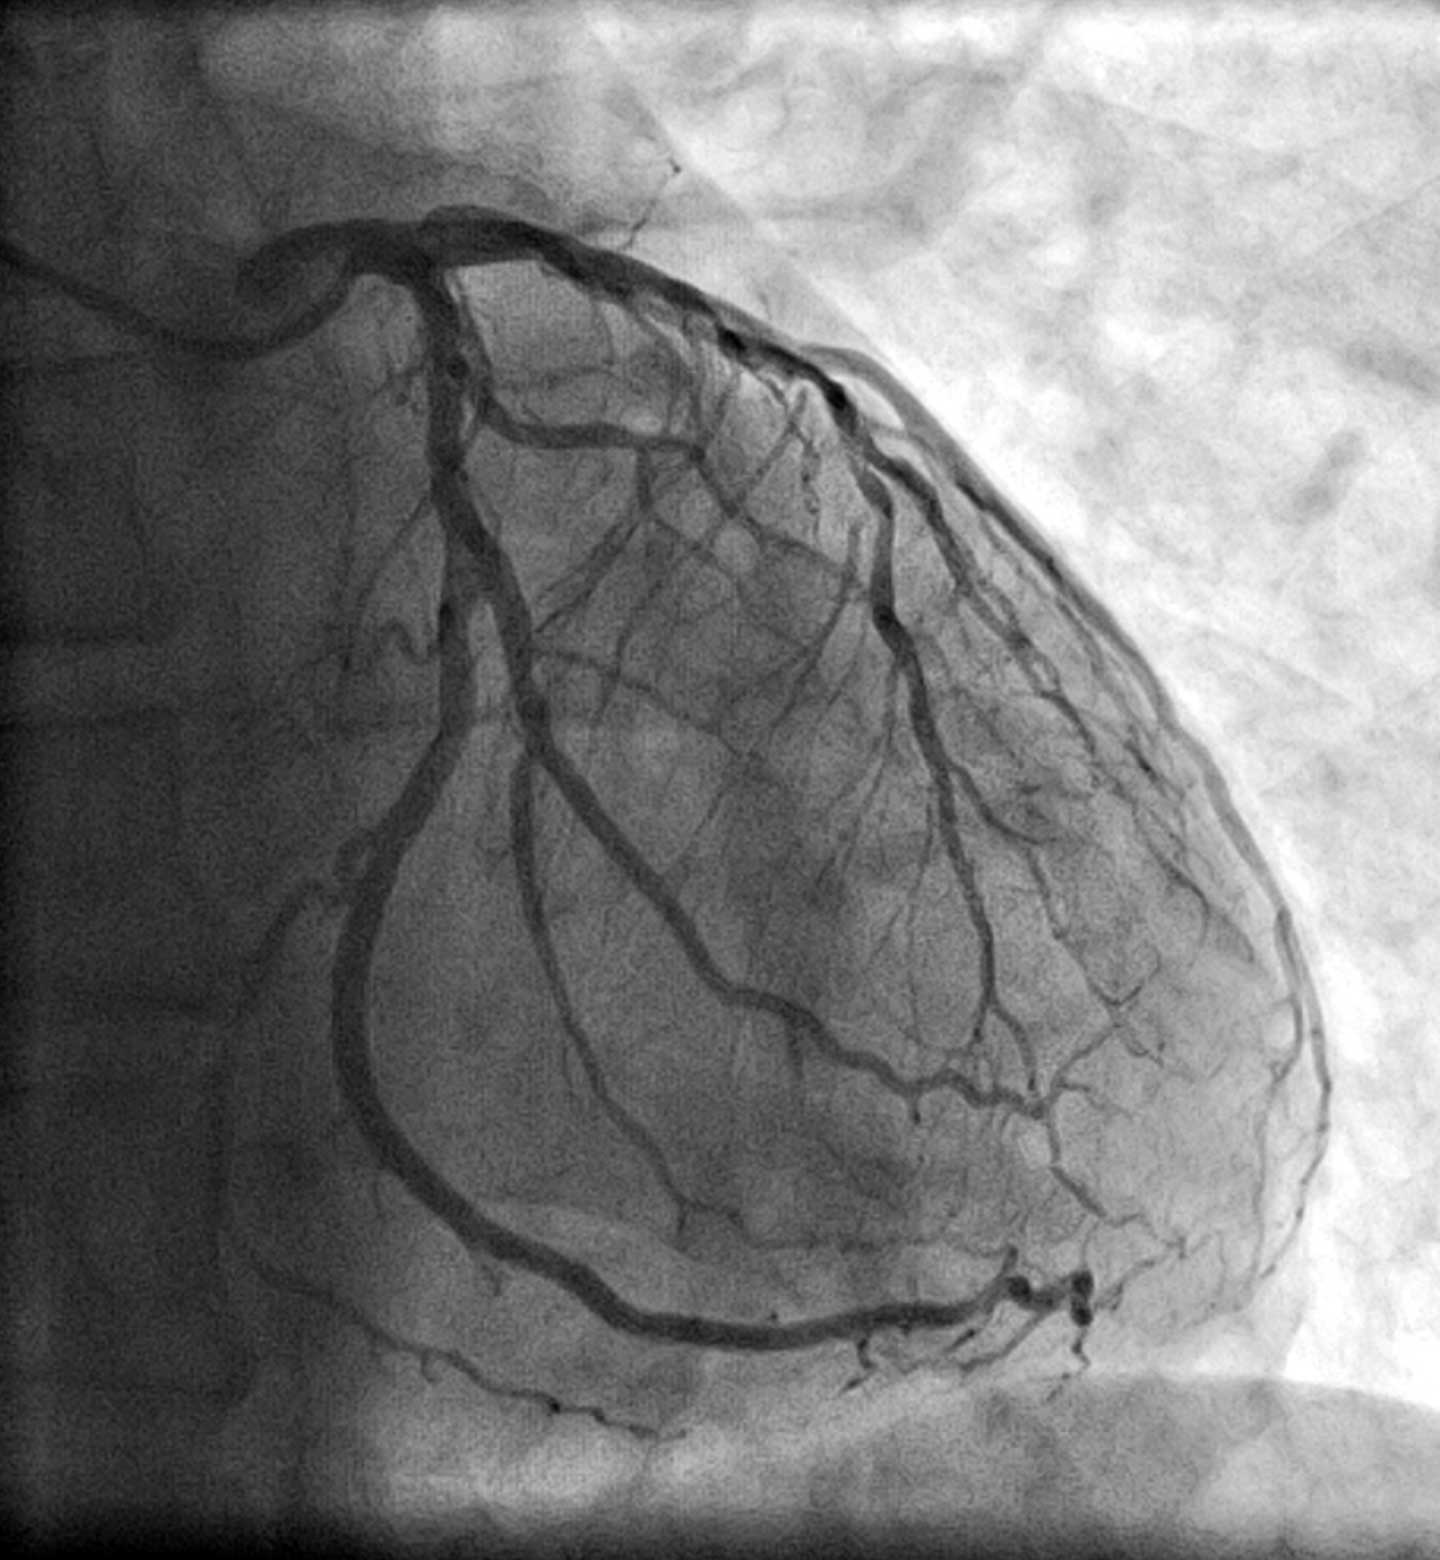

Well, Yes and No. Our recent research, published in JAMA Cardiology used deep neural networks, a type of AI algorithm called CathEF, to predict how much blood a heart was pumping using standard angiogram videos – x-ray images that visualize the inside of blood vessels, in particular arteries, veins and the heart chambers – with the goal of gaining new insights into possible patient treatment in critical situations.

We fed it coronary angiograms of more than 4,000 of patients along with corresponding transthoracic echocardiograms – or coronary ultrasound tests of 3,600 patients. Angiograms and echocardiograms are the standard diagnostic assessment for nearly all heart disease related decision-making, from medications to coronary bypass surgery, so just about everyone with heart and stoke issues has them done.